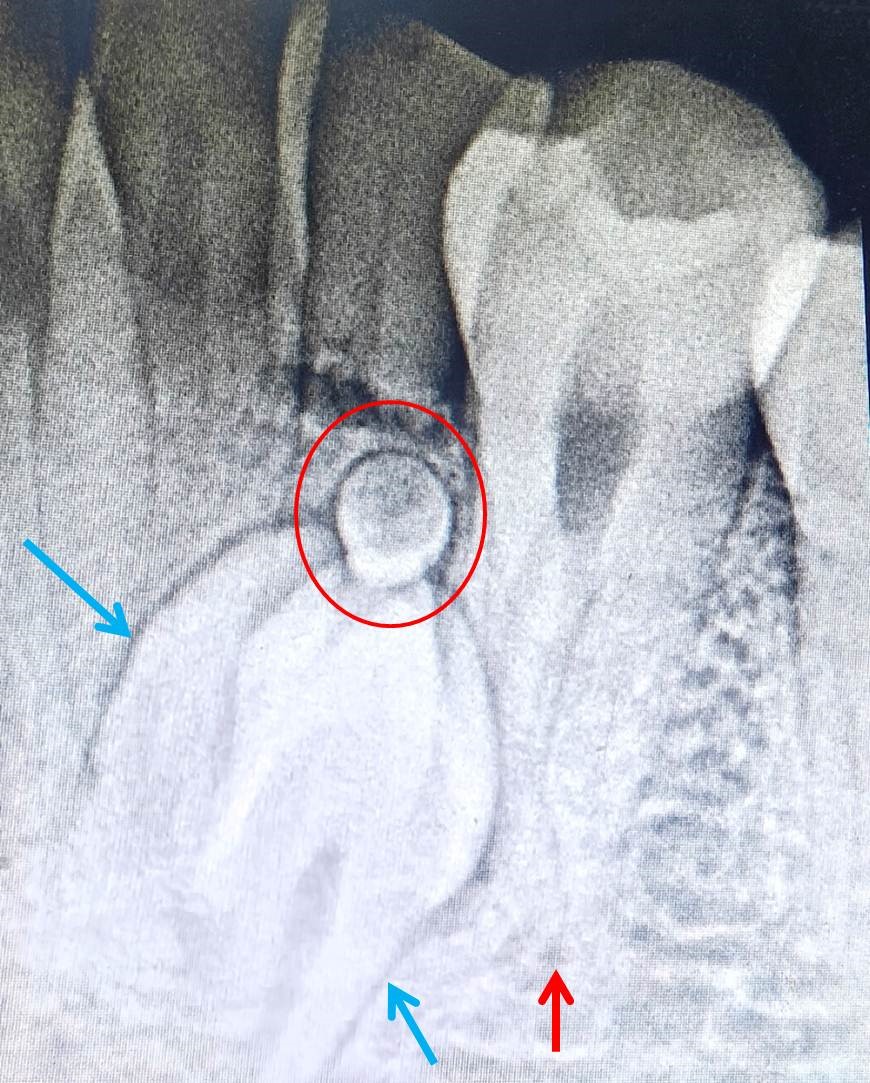

A 18-year-old male patient reported to the Department of Pediatric and Preventive Dentistry, College of Dental Sciences, Davangere, Karnataka, India complaining of dislodged restoration from upper front tooth. Patient was moderately built, well-nourished and did not exhibit any symptoms of systemic, syndromic or metabolic disorders. Patient past history revealed history of dental trauma at the age of 11 years followed by root canal treatment and crown placement for his upper both central incisors. From then patient did not visit dentist and now visited seeking treatment for his dislodged crown. Intraoral examination showed patient with complete permanent dentition except for the presence of retained 73. Permanent 33 was clinically missing. 73 exhibited some degree of mobility. To know the condition of 73 patient was subjected to radio-visuographic examination which revealed presence of small irregular shaped radiopaque masses below the root of 73 and in place of permanent left canine (Figure 1). Radiographic mass exhibited 3-4 small, tooth shaped structures resembling supernumerary teeth (Figure 1). Above these structures, a solitary, small, round shaped radiopaque structure was observed. Regarding root of 73, it exhibited apical one third of root resorption. In addition to these, radiograph also showed half picture of impacted tooth located between right and left central incisors. Hence, to have the complete image of the impacted canine, orthopantomography was taken. Examination of OPG showed rotated and vertically oriented impacted mandibular left canine, its long axis crossing the dental midline. The impacted canine was located below and between roots of two central incisors. Further evaluation of the radiograph showed presence of a supernumerary root in mandibular right first premolar. The two roots were mesial and distally located (Figure 2). Contralateral premolars had single roots. The root of the permanent mandibular right canine exhibited root flexion and aberrant morphology of the root canal Details of morphological oddities are explained in Table 2. No other dental findings were observed. To attend chief complaint of the patient, crown was re-cemented and patient was explained about the existing dental anomalies in his jaw. As all three dental anomalies were asymptomatic, not associated with any pathologic changes periodic observation was advised.

Figure 1: RVG showing combined compound (blue arrows) and complex odontoma (red circle). First premolar with two roots is also evident (red arrow).